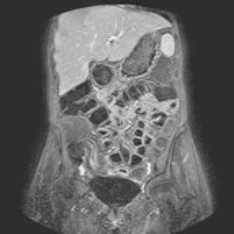

Der Schwerpunkt der MRT liegt in der Darstellung von Weichteilstrukturen, das heißt vor allem von nicht-knöchernen Strukturen. Die häufigsten Einsatzbereiche der Magnetresonanztomographie (MRT) sind die Diagnostik von Erkrankungen der Oberbauchorgane (Leber, Nieren, Nebennieren, Bauchspeicheldrüse), der Lymphknoten, der Gelenke und Muskeln, des Gehirns (inklusive der Gefäße), des Darms, des Herzens und der Gefäße oder auch der Brustdrüse (Mamma). Insbesondere lassen sich Entzündungen oder gut- bzw. bösartige Tumoren hervorragend darstellen. Da die Lunge vorwiegend Luft beinhaltet und die Luft kein Signal im MRT gibt, eignet sich hierfür das CT deutlich besser zur Darstellung.